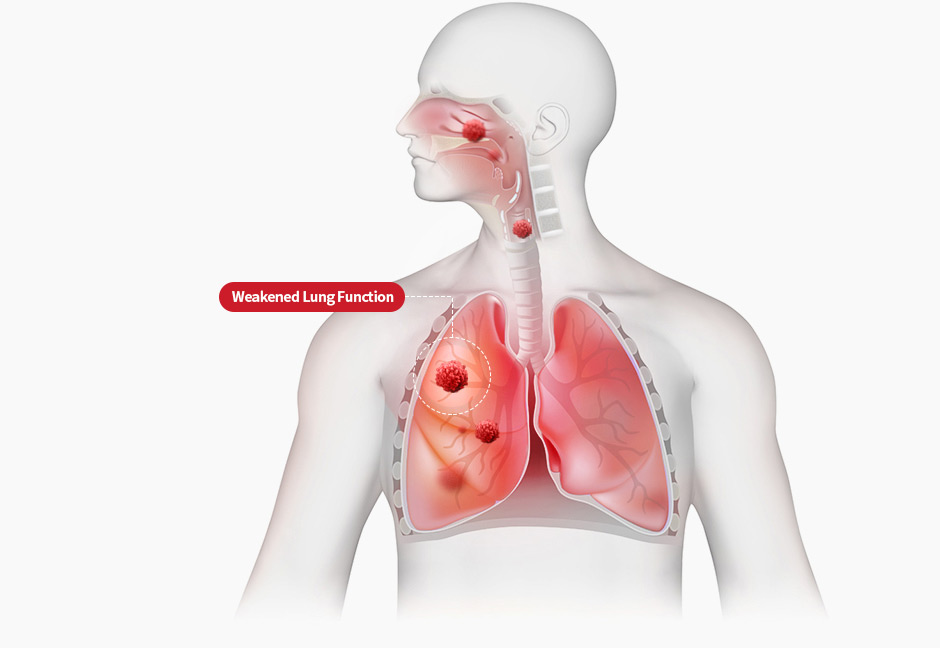

STEP 1

Clogged skin pores

trigger itching

STEP 1

Clogged skin pores

trigger itching

STEP 2

Normalize lung function

with Pyunkang-tang

(Lung function gradually recovers, enabling skin respiration)

STEP 2

Normalize lung function

with Pyunkang-tang

(Lung function gradually recovers, enabling skin respiration)